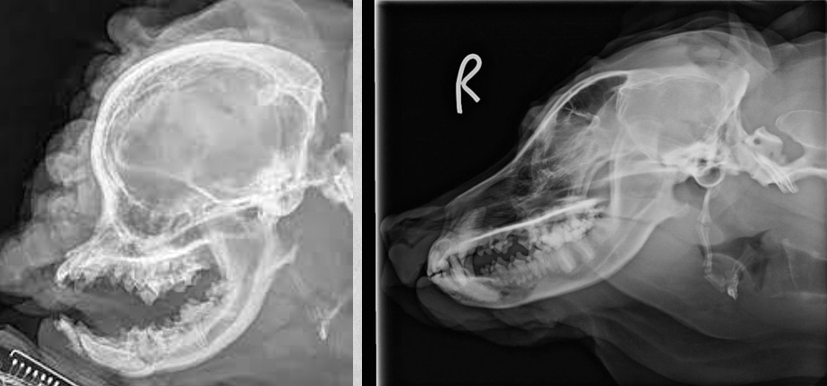

A

fractured mandibula in oblique views

in the right mandibula view you can barely see the fracture due to superimposition of structures so capture both mandibula on their own image.